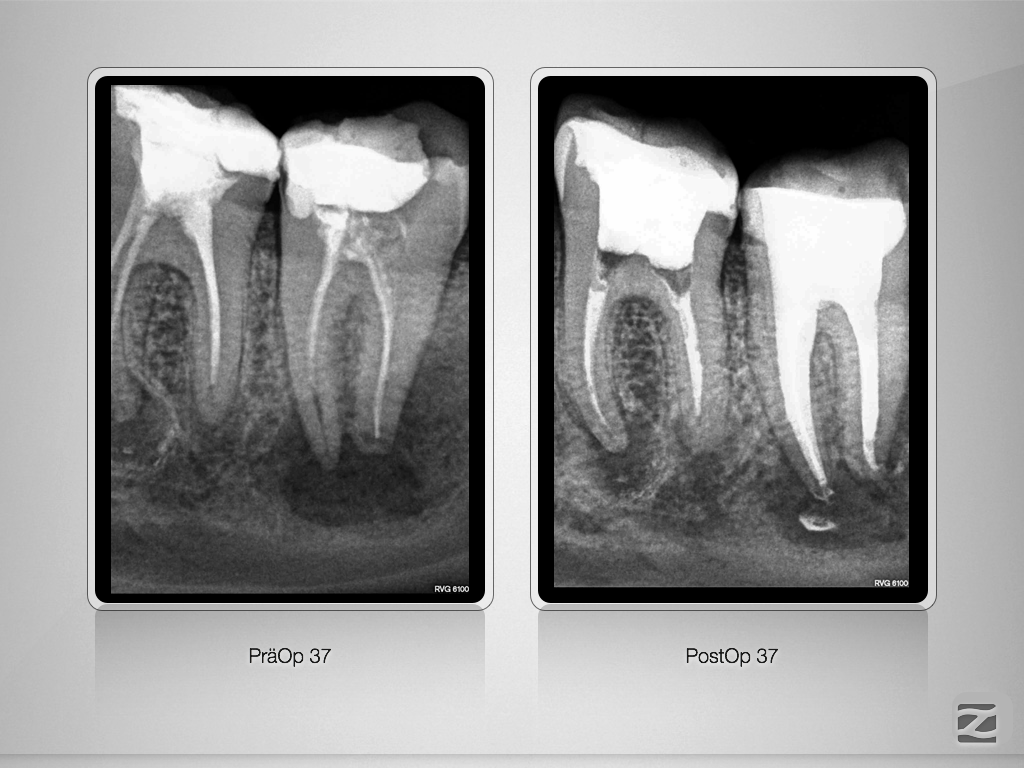

37D.010

Ausgedehnte apikale Lyse